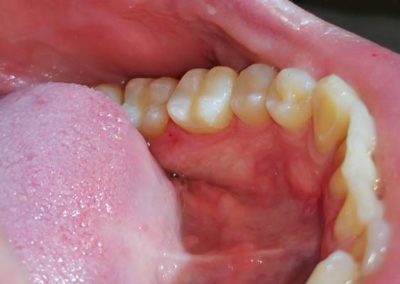

Pacijentu je nedostajao prvi molar u bočnoj regiji. Ovaj zub je posebno značajan i njegov nedostatak narušava kontinuitet celog zubnog luka. Imajući u vidu da su susedni zubi bili zdravi, kao idealno rešenje sa pacijentom je dogovorena ugradnja implanta i protetska nadoknada na implantu.

Na rendgen snimcima prikazana je donja vilica pre ugradnje implanta i donja vilica nakon perioda srastanja (oseointegracije) implanta sa koštanim tkivom.